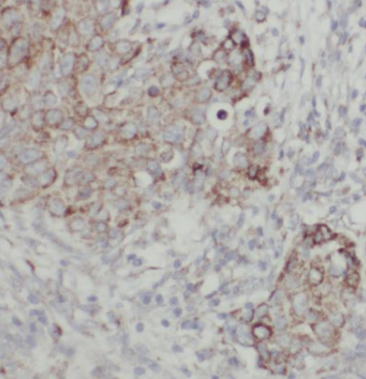

| 验证图片 | Immunohistochemistry of paraffin-embedded human breast cancer tissue slide using FNab01666(CHKA antibody) at dilution of 1:50 COLO 320 cells were subjected to SDS PAGE followed by western blot with FNab01666(Choline kinase alpha-Specific antibody) at dilution of 1:300 |